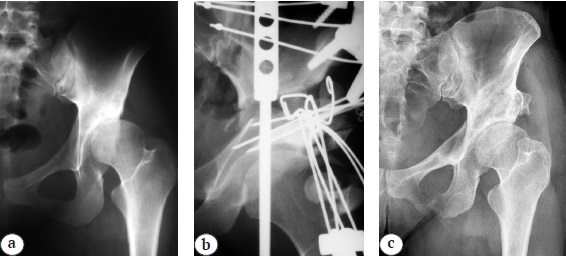

Figure 2 presents a sample case from group 2.

Fig. 2. X-ray images of a 20-year-old patient; dysplastic coxarthrosis, stage II; dislocations, stage II; a — before treatment; b — during treatment; c — 16 years follow-up